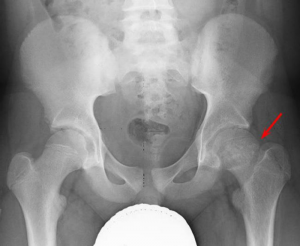

What is it? Slipped Capital Femoral Epiphysis (or SCFE) is a hip issue affecting older children and younger teenagers. It is a fracture of the growth plate …